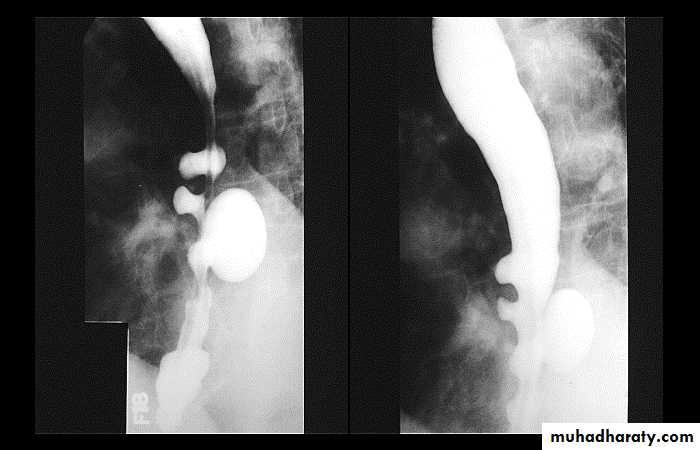

Sliding herniaOn the left initially, GE junction is below the esophageal hiatus. Later, stomach protrudes through hiatus

Para esophageal hernia

On the far left gas filled gastric funds (asterisk) protrudes through hiatus but GE junction (arrow) is below diaphragm